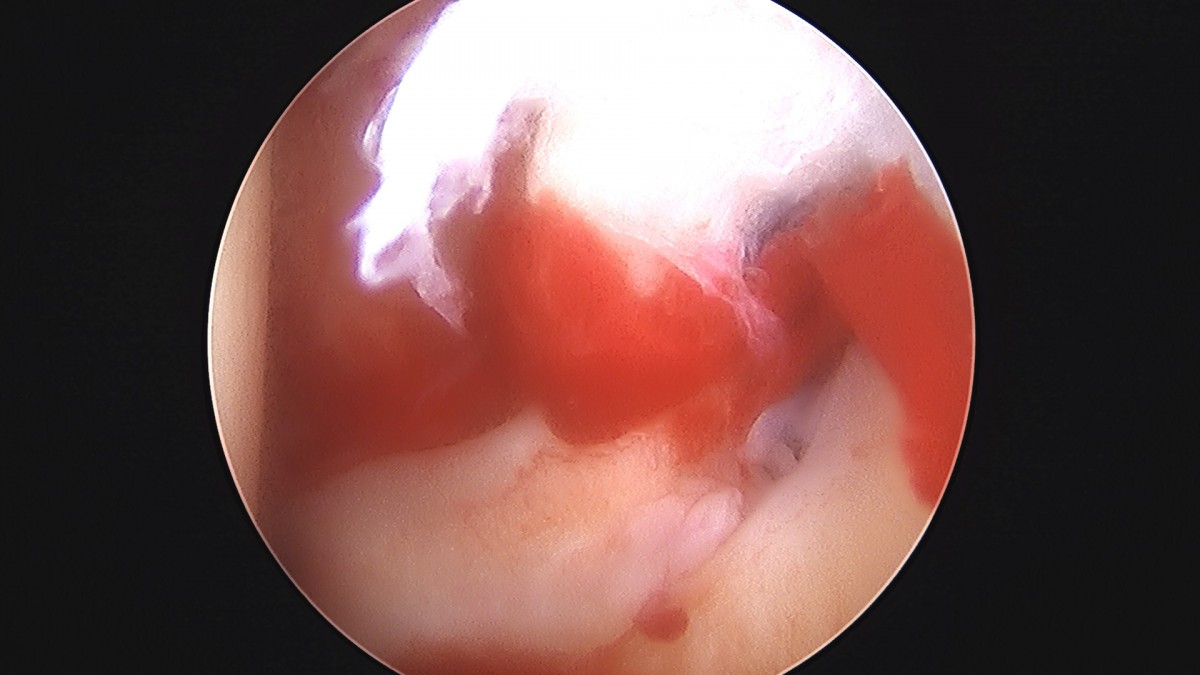

정지영원장님 어깨 관절낭 이완술 및 석회제거술 박설O 환자

작성자 최고관리자 댓글 0건 조회 732회 작성일 25-09-16 16:59